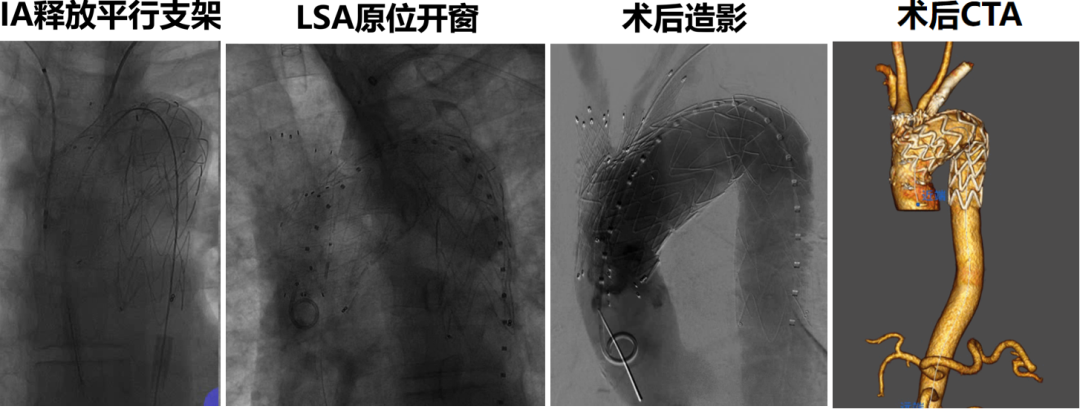

★ Case1:胸主动脉夹层动脉瘤,带分支支架重建LSA+平行支架重建LCCA

★ Case2:胸主动脉瘤,带分支支架重建LCCA+原位开窗技术重建LSA

★ Case3:B型主动脉夹层,带分支支架重建LCCA+体外开窗技术重建LSA

★ Case4:主动脉弓部溃疡,带分支支架重建LCCA+平行支架IA+颈锁搭桥重建LSA

★ Case5:主动脉弓部溃疡,带分支支架重建LCCA+平行支架重建IA+原位开窗重建LSA